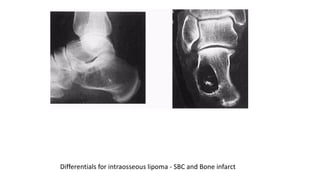

Plain radiograph feature

• Expansile radiolucent lesion with sharply defined

• sclerotic margin

• • No periosteal new bone formation

• Within calcaneum, lipoma has characteristic

• appearance, osteolytic lesion with a central focus

• o f o s s i fi c a t i o n

• CT & MRI

• • Can be homogenous fat content

• • Fatty lesion with central necroses, central

• calcifications o r o s s i fi c a t i o n s

• • Fatty lesion with multiple central necroses, central

• calcifications or ossifications

Differentials for intraosseous lipoma - SBC and Bone infarct